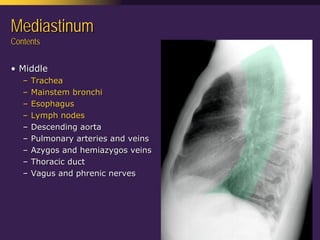

This document discusses mediastinal pathology using a compartmental approach. It describes the anatomy of the mediastinum and divides it into anterior, middle, and posterior compartments. Each compartment contains different structures and has a characteristic distribution of lesions. For example, 50% of lesions occur in the anterior compartment, which contains the thymus. The thymus is the most common site of lesions in the anterior compartment. Thymomas are the most common epithelial tumors of the thymus and mediastinum.